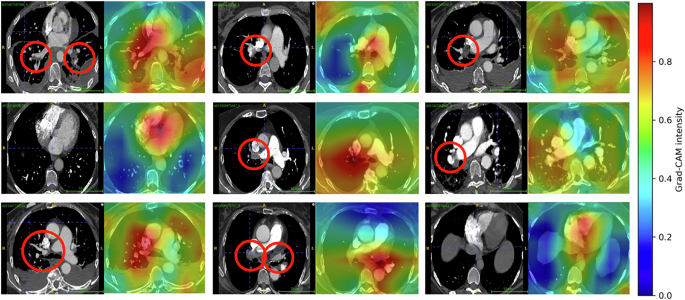

PE classifier grad-CAM visualization results

We employed gradient back-propagation techniques for model interpretability. We highlighted the features selected by the model during prediction and identified locations and slices in the 3D-CTPA imaging scan that contributed the most to the classification using 3D gradient-weighted class activation mapping31. For our implementation we used Captum open source package, an extensible library for model interpretability built on PyTorch32. Figure 8 illustrates the heatmap visualizations generated by back-propagating through the 3D PE classification model - highlighting areas that most influenced the model’s decision. We anticipated that the model would focus on regions associated with PE as well as descriptors correlated with high-risk PE, such as the heart region and hepatic veins. As expected, the network concentrated on areas containing PE clots and the heart (particularly the right and left ventricular (RV, LV) chambers). We note that the Grad-CAM predictions cover a broader region around the PE clots, resulting in less precise localization. We hypothesis this is due to performing the classification in the latent space, where spatial resolution is naturally lower.

Presented are samples of Grad-CAM and original slices. For each sample, we paired the original CTPA slice (left) with the corresponding Grad-CAM overlay on the matching generated slice (right). Red circles indicate the precise PE locations as identified by an experienced radiologist. High activations (red, yellow and green) indicate the focus areas that the model selected for classification. Note the high activations around PE clots and the heart area.